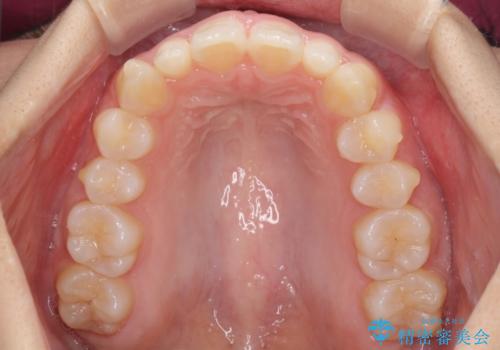

前歯のデコボコを治したい インビザラインによる矯正治療

- 前歯のデコボコ気になるとのことで来院された患者様です。

上下顎ともに歯列全体の後方移動とIPR(歯と歯の間を削る)によってデコボコが解消するように設計し、インビザラインにより治療を行うこととしました。

上顎左右前歯に矮小歯があるため、上顎の奥歯は下顎に対して相対的に前方に位置することになりました。

それでも奥歯の咬みにくさはなく、患者様には大変満足していただきました。